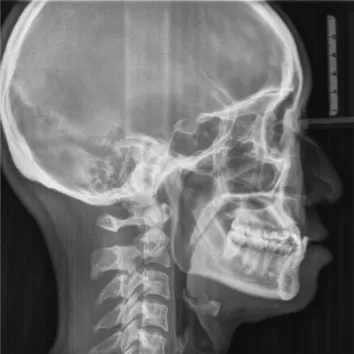

Rayons X avant le traitement

[Radiographie panoramique/Céphalogramme latéral]